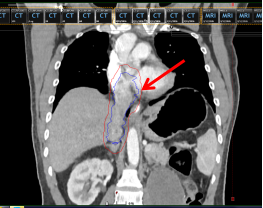

图2 癌栓(图中红色剪头所指蓝色框内区域)